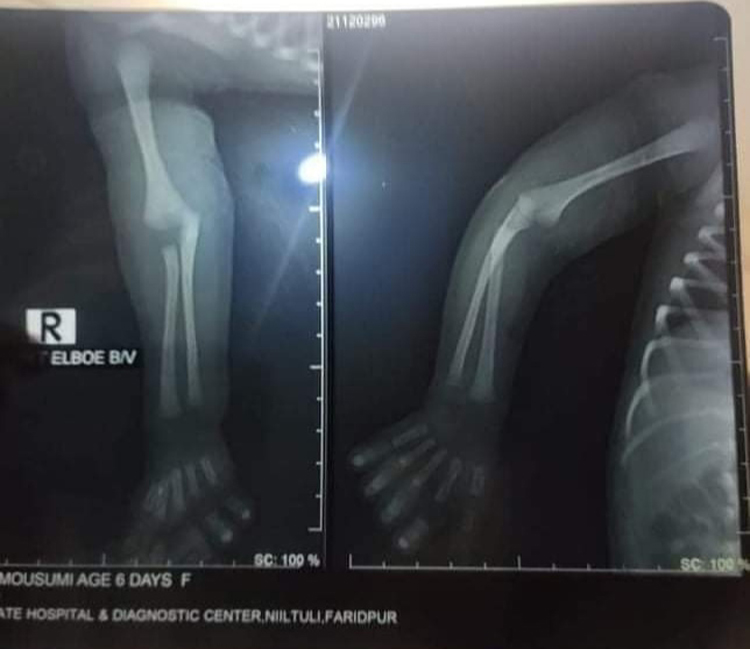

অভিযোগ সূত্রে জানা গেছে, ১৩ ডিসেম্বর হাসপাতালটিতে সিজারের জন্য তার প্রসূতি স্ত্রীকে ভর্তি করা হয়। ভর্তির পরপরই তাকে অপারেশন থিয়েটারে নিয়ে যাওয়া হয়। ডা. শারমিন সুলতানা জুই এ সিজার করেন। কিন্তু সিজার চলাকালে চিকিৎসকের অবহেলায় নবজাতকের হাতের কনুই থেকে হাড়ের জয়েন্ট ছুটে যায়। হাসপাতাল থেকে বের হওয়ার সময় হাসপাতাল কর্তৃপক্ষ কোনো কিছু না জানানোয় ভুক্তভোগীরা স্বাভাবিকভাবে ছাড়পত্র নিয়ে হাসপাতাল ত্যাগ করেন। পরের দিন নবজাতকটি অতিরিক্ত কান্না করতে থাকলে শিশু বিশেষজ্ঞ খ. ডা. মো. আব্দুল্লা হিস সায়াদ কাছে নিয়ে গেলে তিনি ল্যাবএইড হাসপাতালের ডা. সৈয়দ আসিফ উল আলম সাহেবের কাছে রেফার করেন।

ডা. সৈয়দ আসিফ উল আলম সাহেব ঢাকা হেলথ অ্যান্ড হোপ হাসপাতালের অধ্যাপক ডা. সারোয়ার ইবনে সালামের কাছে রেফার করেন। বর্তমানে সেখানেই নবজাতকের চিকিৎসা চলছে। চিকিৎসক জানান সিজারের সময় ডাক্তারদের অবহেলার কারণেই বাচ্চার হাতের কনুই থেকে হাড় আলাদা হয়ে যায়।